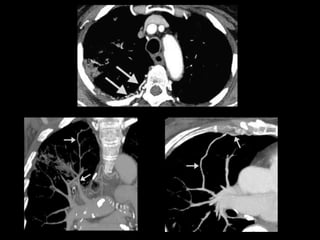

Protocolo AngioTC Torácico

• Desde base cuello hasta nivel de arterias renales

para incluir troncos supraaórticos y arterias

infradiafragmáticas.

• 0.8/1 mm. grosor de corte

• 100-120 ml contraste yodado no iónico a 4cc/sg.

• ROI en Aorta descendente.

• Reconstrucciones multiplanares y volumétricas

(MIP y VR): coronales (arterias mamarias internas

e intercostales) y axiales (arterias frénicas

inferiores y tronco celiaco).

Protocolo AngioTC Torácico •Desde base cuello hasta nivel de arterias renales para incluir troncos supraaórticos y arterias infradiafragmáticas. • 0.8/1 mm. grosor de corte • 100-120 ml contraste yodado no iónico a 4cc/sg. • ROI en Aorta descendente. • Reconstrucciones multiplanares y volumétricas (MIP y VR): coronales (arterias mamarias internas e intercostales) y axiales (arterias frénicas inferiores y tronco celiaco).